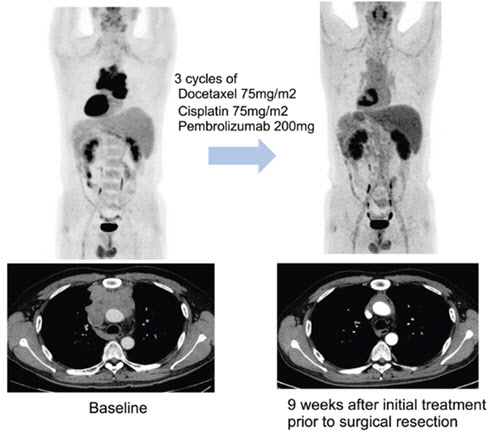

수술에 앞서 3주 간격으로 세 차례 항암화학요법에 면역항암제 펨브롤리주맙을 병용 투여한 결과병리학적으로 완전 관해를 보인 환자 예시. 연구팀은 이 환자가 3기 흉선암이었으나 현재 3년 이상 재발 없이 경과 관찰 중이라고 밝혔다. 연구팀은 “수술 시행한 환자 중 약 18%의 환자에서 완전 관해, 약 46%의 환자에서는 잔여 생존암이 10% 이하인 주요 부분 관해(major pathologic response)가 관찰됐다”고 밝혔다. |

연구팀은 이들 환자에게 3주 간격으로 세 번에 걸쳐 기존 항암화학요법에 펨브롤리주맙을 병용 투여한 다음 수술 가능 여부를 평가했다. 수술 후에는 최대 32주간 펨브롤리주맙 유지하는 한편, 일부는 항암방사선치료를 더하는 식으로 치료가 진행됐다.